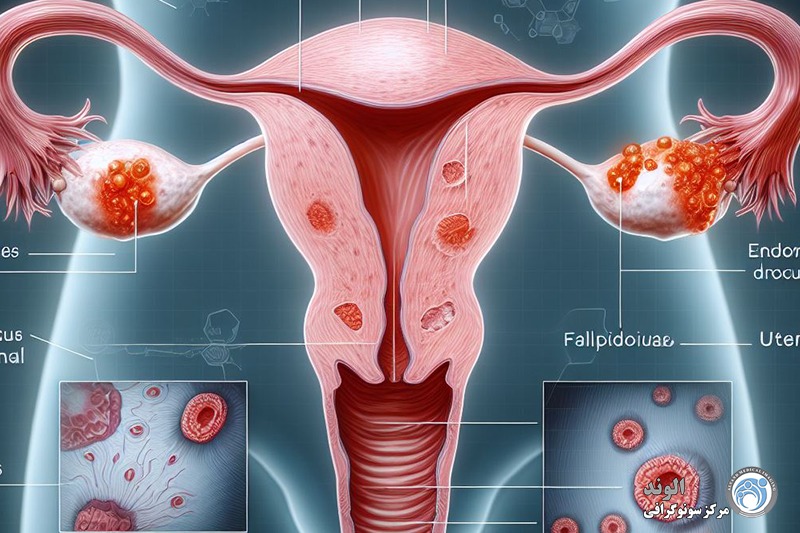

این بیماری زمانی اتفاق میافتد که بافت مشابه با بافت داخلی رحم (آندومتر) در جایی خارج از رحم رشد میکند، معمولاً در تخمدانها، لولههای فالوپ یا سایر اندامهای لگنی. علائم آندومتریوز میتواند شامل دردهای شدید قاعدگی، درد در حین رابطه جنسی، مشکلات باروری و خونریزی غیر طبیعی باشد. با این حال، بسیاری از زنان مبتلا به آندومتریوز ممکن است بدون علائم جدی یا فقط علائم خفیف داشته باشند، که این ممکن است تشخیص بیماری را دشوار کند.

اندومتریوز یک بیماری زنان است که در آن بافتی مشابه به بافت داخلی رحم (اندومتر) در خارج از رحم رشد میکند. این بیماری میتواند به شدت دردناک باشد و مشکلاتی چون ناباروری، دردهای مزمن لگنی، و اختلالات قاعدگی را ایجاد کند. تشخیص زودهنگام اندومتریوز اهمیت زیادی دارد زیرا میتواند به مدیریت مؤثرتر علائم و بهبود کیفیت زندگی بیماران کمک کند. یکی از روشهای رایج و غیرتهاجمی برای تشخیص اندومتریوز استفاده از سونوگرافی است که به ویژه در شناسایی برخی از ویژگیهای این بیماری بسیار مؤثر است.

مرحله اول: در این مرحله، ضایعات بسیار کوچک و بهصورت محدود دیده میشوند. این نشانهها اغلب اولیه و خفیف هستند.

مرحله دوم: ضایعات کمی گستردهتر شده و ممکن است در چند نقطه از بدن وجود داشته باشند. احتمال ایجاد چسبندگی در این مرحله وجود دارد.

مرحله سوم: در این وضعیت، ضایعات یا بهصورت سطحی گسترده هستند یا به شکل عمقی گسترش یافتهاند. در این مرحله چسبندگیها بهصورت واضحتر مشاهده میشوند و ممکن است علائم بالینی نیز شدیدتر باشند.

مرحله چهارم: پیشرفتهترین و شدیدترین مرحله بیماری است. در این مرحله، ضایعات هم سطحی و هم عمقی هستند و در نواحی مختلف گسترش یافتهاند. چسبندگیها در این مرحله بسیار زیاد و گستردهاند و معمولاً با درد و اختلال عملکرد اندامهای درگیر همراه هستند.

تشخیص دقیق معمولاً از طریق معاینه بالینی، تصویربرداری مانند سونوگرافی یا MRI و گاهی لاپاراسکوپی انجام میشود تا شدت بیماری مشخص شود و درمان مناسب انتخاب گردد.

در آندومتریوز، سلولهای آندومتر فعال در لگن خارج از حفره رحم کاشته میشوند. علائم به محل کاشت بستگی دارد. سه گانه کلاسیک علائم، دیسمنوره، دیسپارونی و ناباروری است، اما علائم ممکن است شامل سوزش ادرار و درد در هنگام اجابت مزاج نیز باشد. شدت علائم ربطی به مرحله بیماری ندارد. تشخیص با تجسم مستقیم و گاهی بیوپسی، معمولاً از طریق لاپاراسکوپی است. درمانها شامل داروهای ضدالتهابی، داروهایی برای سرکوب عملکرد تخمدان و رشد بافت آندومتر، ابلیشن جراحی و برداشتن ایمپلنتهای اندومتریوتیک، و اگر بیماری شدید است و برنامه ریزی برای بچهدار شدن وجود ندارد، هیسترکتومی به تنهایی یا هیسترکتومی به علاوه سالپنگو اوفورکتومی دوطرفه.

اندومتریوز معمولاً به سطوح صفاقی یا سروزی اندامهای لگنی، معمولاً تخمدانها، رباطهای پهن، کولدساک خلفی و رباطهای رحمی خاجی محدود میشود.

محل های کمتر شایع شامل لوله های فالوپ، سطوح سروزی روده کوچک و بزرگ، حالب، مثانه، واژن، دهانه رحم، اسکارهای جراحی و به ندرت ریه، پلور و پریکارد می باشد.

در آندومتریوز، سلولهای آندومتر فعال در لگن خارج از حفره رحم کاشته میشوند. علائم به محل کاشت بستگی دارد. سه گانه کلاسیک علائم، دیسمنوره، دیسپارونی و ناباروری است، اما علائم ممکن است شامل سوزش ادرار و درد در هنگام اجابت مزاج نیز باشد. شدت علائم ربطی به مرحله بیماری ندارد. تشخیص با تجسم مستقیم و گاهی بیوپسی، معمولاً از طریق لاپاراسکوپی است. درمانها شامل داروهای ضدالتهابی، داروهایی برای سرکوب عملکرد تخمدان و رشد بافت آندومتر، ابلیشن جراحی و برداشتن ایمپلنتهای اندومتریوتیک، و اگر بیماری شدید است و برنامه ریزی برای بچهدار شدن وجود ندارد، هیسترکتومی به تنهایی یا هیسترکتومی به علاوه سالپنگو اوفورکتومی دوطرفه.

اندومتریوز معمولاً به سطوح صفاقی یا سروزی اندامهای لگنی، معمولاً تخمدانها، رباطهای پهن، کولدساک خلفی و رباطهای رحمی خاجی محدود میشود.

محل های کمتر شایع شامل لوله های فالوپ، سطوح سروزی روده کوچک و بزرگ، حالب، مثانه، واژن، دهانه رحم، اسکارهای جراحی و به ندرت ریه، پلور و پریکارد می باشد.